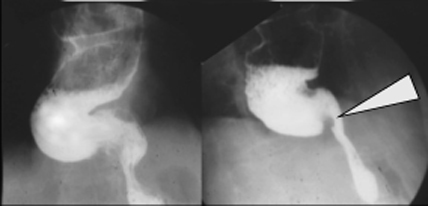

Diverticule epiphrenique :

Situee 1/3 inferieure , oesophage achalasia et image

arrondie remplie par baryte du diverticule |

Situe

souvent a droite sus diaphragmatique |

Image en niveau d'une

diverticule de oesophage . Elle ne se vide pas

|